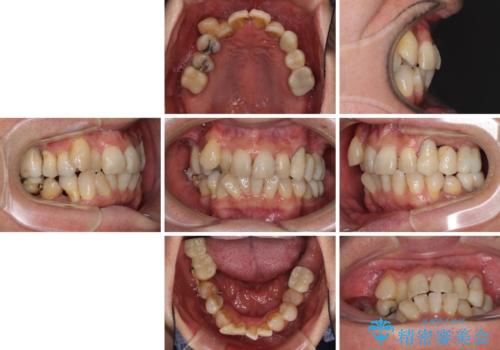

- 歯並びやグラグラする奥歯など、気になる所を全部治したいとのことで来院された患者様です。

奥歯は咬み合わせや歯周病により歯槽骨が失われていたり、むし歯や破折している歯などがあったりと、歯周病治療やインプラント補綴、矯正治療など、総合的に治療が必要と診断されました。

まずは歯周病治療やインプラント埋入を行い、環境が整った後にワイヤーを併用したインビザライン矯正を行い、オールセラミッククラウンにて補綴治療を行うこととしました。

初診時に4年かかりますとお伝えし、実際に4年数ヶ月を要する治療となりました。

治療中は仮歯が頻繁に脱落したり、歯周外科によりむき出しとなった歯根が知覚過敏を起こしたりと、苦労は絶えませんでしたが、4年の治療の後にスッキリと仕上げることができました。